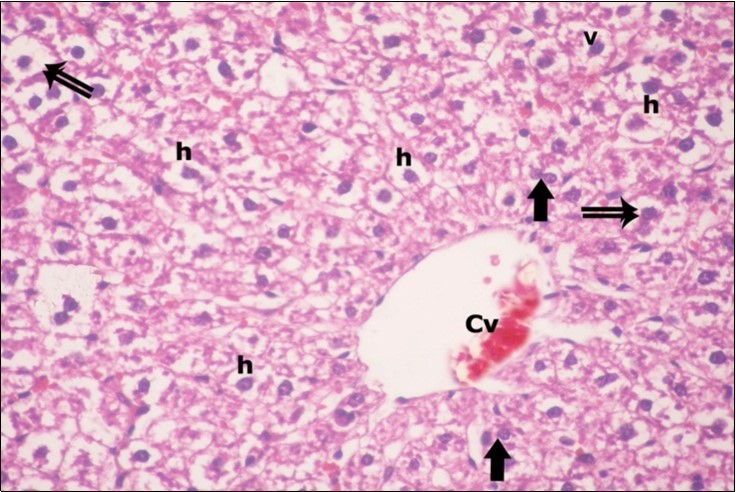

Examination of H&E stained sections of the 1st group (control group) revealed hepatic architecture of tightly packed cords of hepatocyte with vesicular nuclei and acidophilic cytoplasm radiating from the central vein (Figure 1). Portal area was composed of a portal vein, branch of hepatic artery and bile duct lined by single cuboidal cells with dark rounded nuclei. Blood sinusoids with their endothelial lining of Kuppfer cells were noticed in between hepatic cords (Figure 2). Examination of the liver sections of the 2nd group (vitamin E treated group) showed nearly the same histological features as the 1st group. The 3rd group (ZnONPs-treated group) showed a marked loss of the normal liver arrangement with dilated congested central veins and blood sinusoids. Most of hepatocytes had large cytoplasmic vacuoles and darkly stained nuclei other hepatocytes were ballooned (Figure 3). The portal area showed dilated congested portal vein with proliferation of bile duct, necrotic foci in between the hepatocytes with inflammatory cellular infiltration (Figure 4). The portal area showed also elongation of the endothelial lining of dilated congested portal vein and increasing amount of connective tissue fibers (Figure 5). There was congested hepatic artery with increasing thickness of its muscular layer (Figure 6). Bile duct showed proliferation with stratification of its epithelial lining (Figure 7).

Figure 3.A photomicrograph of a section in the liver of ZnONPs-treated adult albino rat showing dilated congested central vein (Cv) and ballooning of hepatocytes (double arrows) with darkly-stained nuclei (h) and vacuolated cytoplasm (v). Binucleated cells are also seen (thick arrows). (H&E X400)

In the present work, H&E-stained liver sections of the ZnONPs-treated group showed disruption of normal architecture with congestion and dilatation of central as well as blood sinusoids. These results are in accordance with Johar et al., 28 who suggested that the destruction of lobular structure, vacuolization of hepatocytes (fat deposits), and infiltration of leukocytes indicate necrotic effects of ZnONPs on liver tissue. On the other hand, Puche et al., 29 attributed sinusoidal dilatation to the activation of perisinusoidal cells which had contractile properties. On contrary to the current results, Wang et al 26 found minimal toxicity through their biodistribution assays in liver tissue of mice exposed to 50 and 500 mg/kg ZnONPs.

Some hepatocytes appeared ballooned with dark stained nuclei. This finding is in consistence with Abbasalipourkabir et al., 30 who gave 50, 100, 150 and 200 mg/kg ZnONPs attributed ballooning of hepatocytes to apoptosis induced by ZnONPs. Ma et al. 31 revealed that swelling of hepatocytes indicates that these nanoparticles may affect permeability of the cell membrane in hepatocytes. Al-Rasheed et al., 13 stated that the liver of rats treated with a high dose of ZnONPs showed numerous hepatocytes with karyolysis and pyknotic nuclei in addition to inflammatory cellular infiltration.